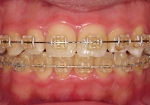

低摩擦クリア矯正装置

設定した治療ゴールにすばやく到達するためには,歯を低摩擦(ローフリクション)で移動させることが重要です.当院では「ローフリクションtypeのブラケットシステム」を採用しています.